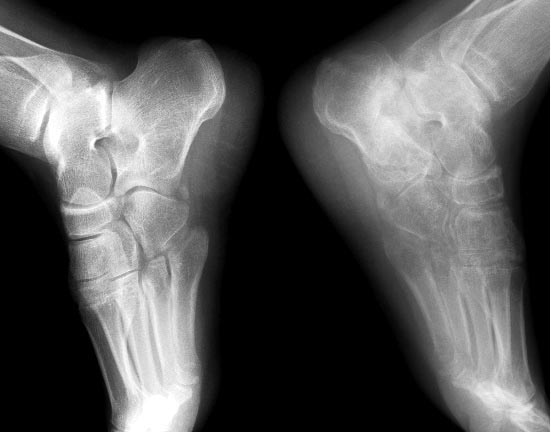

Неправильно консолидированный перелом пяточной кости. |

Приветствую, форумчане! С уважением к вашим знаниям прошу консультации в представленном случае. Пациент, мужчина, 33 года. Травма 6 месяцев назад, падение с 2-х метров на ноги. Лечение: иммобилизация гипсовой лонгетой 3 месяца. В настоящий момент обратился с жалобами на боли при ходьбе, которые появляются через 30-40 минут. Опорная функция сохранена. Пальпируется костная мозоль по наружной поверхности пяточной кости, как следствие, не может носить одинаковую обувь. Рентгенограммы только в одной проекции обеих стоп. Что делать дальше?

1) Имеется посттравматический артроз таранно-пяточного сустава. Пора артродеза или еще рано? 2) Нужны ли дополнительные обследования и какова их цель? 3) Делать ли остеотомию пяточной кости или это чересчур агрессивно?

30-40 мин. без боли через 3 мес. после прекращения иммобилизации - совсем неплохо. Вы совсем не пишете где болит. Если в области латеральной стенки, которую Вы называете мозолью, так ее давление на сухожилия малоберцовых мышц - одна из самых частых причин болей после таких переломов. Убрать эту выпуклость, восстановить пространство для сухожилий - это может решить проблему. Артроза подтаранного сочленения через такой маленький срок еще не бывает. Нарушение конгруэнтности суставных поверхностей - да. Здесь можно сделать диагностическую блокаду и посмотреть на эффект. И конечно - КТ, которая поможет многое понять. Говорить про остеотомию, не имея ничего, кроме не конкретизированной жалобы на боль и снимка в одной проекции, оснований нет.